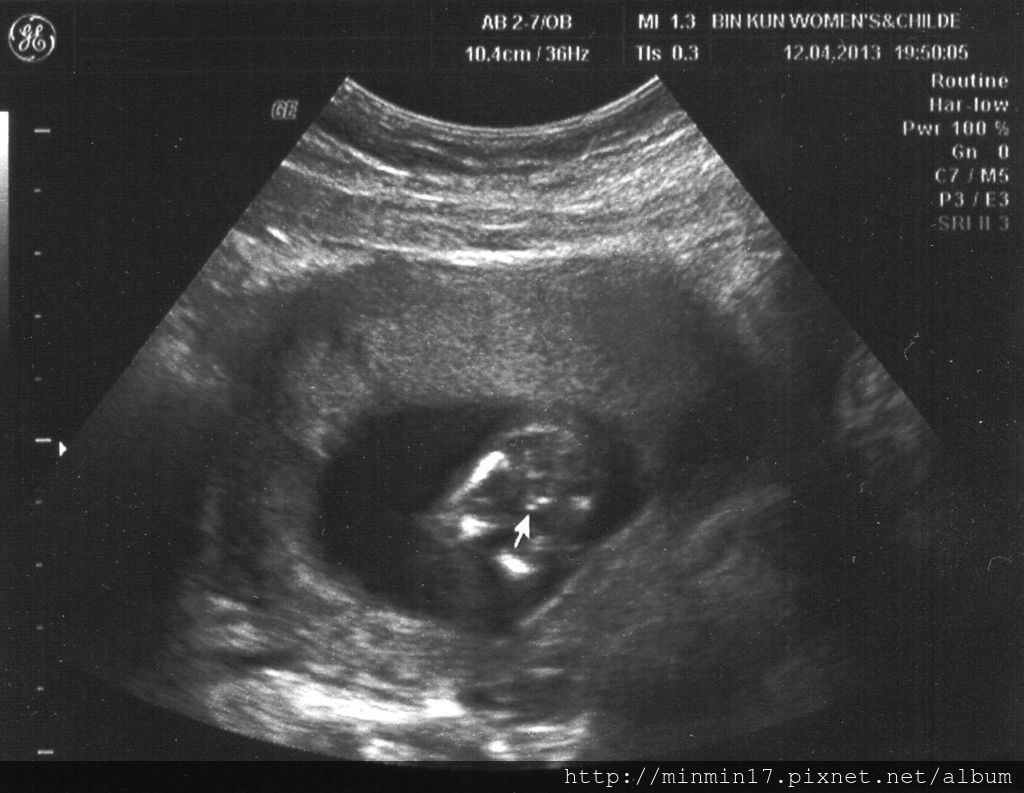

1020412-Little one-7.54cm-14w-Doctor said little one may be a little boy